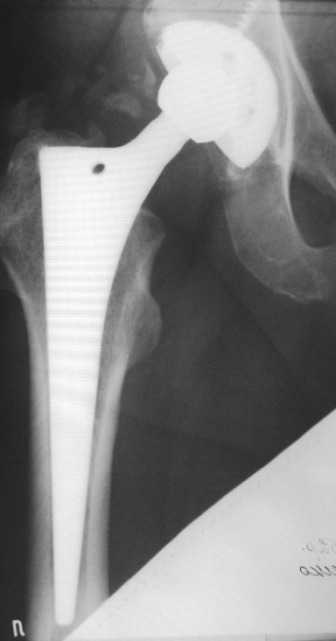

Больной 1952 г.р. тотальное эндопротезирование обеих т/б суставов. Правый 2004г., левый в 2007г. 19.01.09. стали беспокоить боли в средней трети левого бедра по наружной поверхности. Боли беспокоят только при ходьбе. Лежа и сидя болей нет. Стоя вертикально, перенеся массу тела на правую ногу боль исчезает, при равномерном распределении нагрузки снова появляется. Снимки прилагаю. Заранее всем благодарен за оказанную помощь.